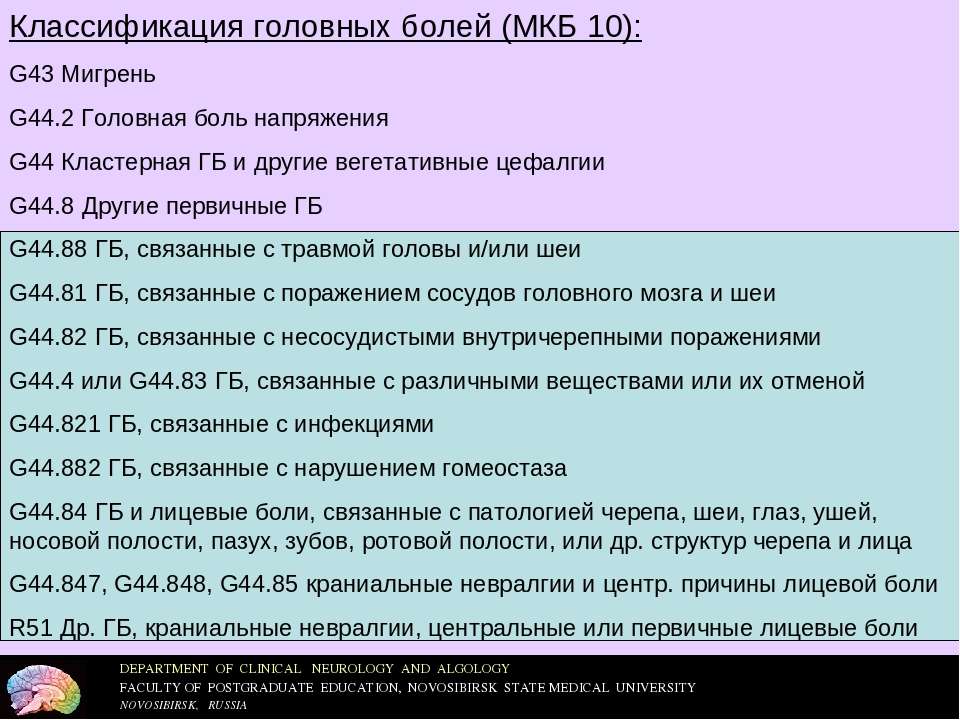

Код мкб 10 атерома головы

Код мкб 10 атерома головы 109 фото